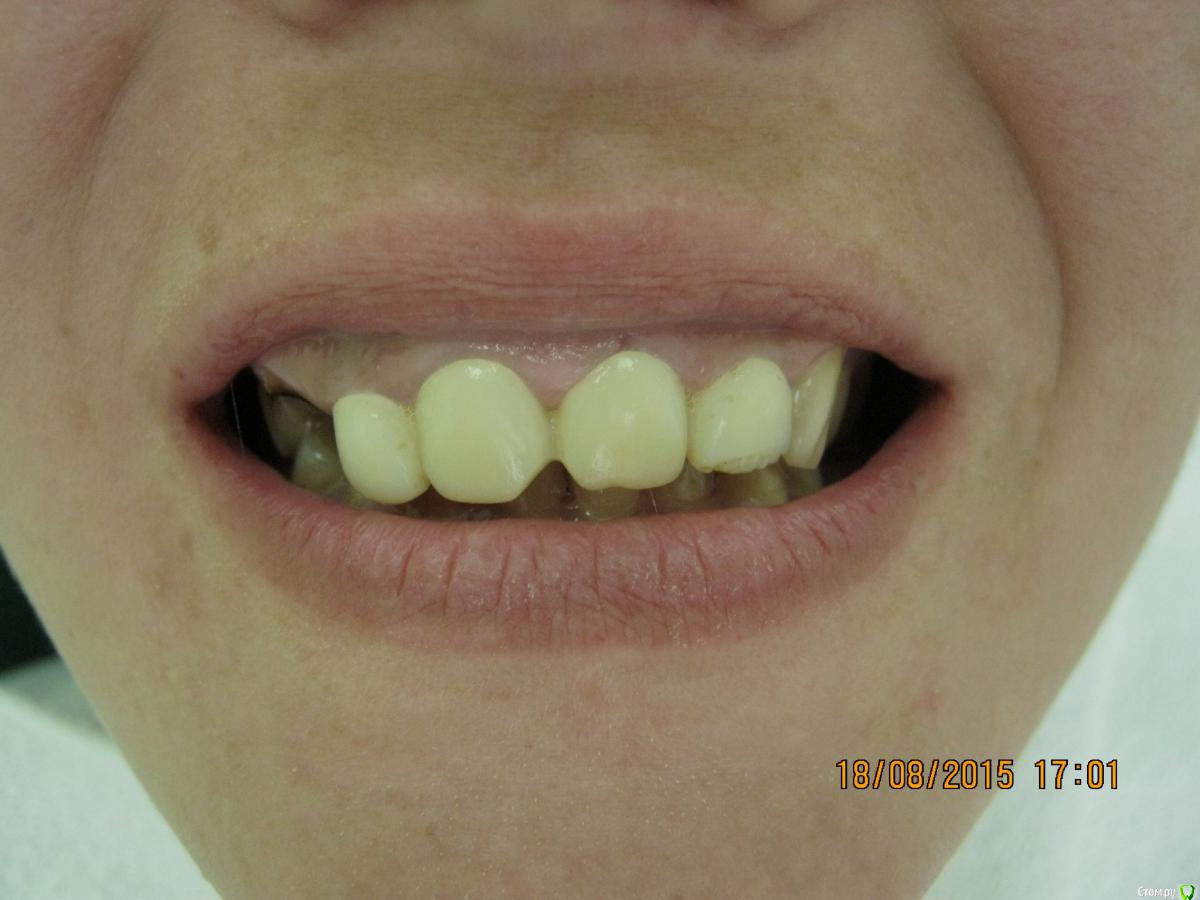

SeregaStomatolog Опубликовано 18 августа, 2015 Поделиться Опубликовано 18 августа, 2015 Добрый вечер уважаемые коллеги!В клинику обратилась пациентка с такой ситуацией во рту.Подскажите пожалуйста что можно сделать и с чего начать. Ссылка на комментарий

SeregaStomatolog Опубликовано 18 августа, 2015 Автор Поделиться Опубликовано 18 августа, 2015 Во-первых она хочет нормально улыбаться,не стесняясь отсутствующего клыка.Во-вторых она хочет нормально жевать,т.к. отсутствие 1.7,1.6 не позволяет это делать.Я сразу сказал пациентке что вариантов без ортодонтии мало (если они вообще есть) и обещать ничего не стал.Случай сложный,поэтому хочется узнать в принципе,на будущее,какие варианты лечения возможны (если можно по подробнее).Пока что я снял слепки,отлил модели-пошел за советом к коллегам в другую клинику-все настаивают на ортодонтии.Теперь вся надежда на Вас коллеги,подскажите что можно придумать более менее приемлемое без ортодонтии. Ссылка на комментарий